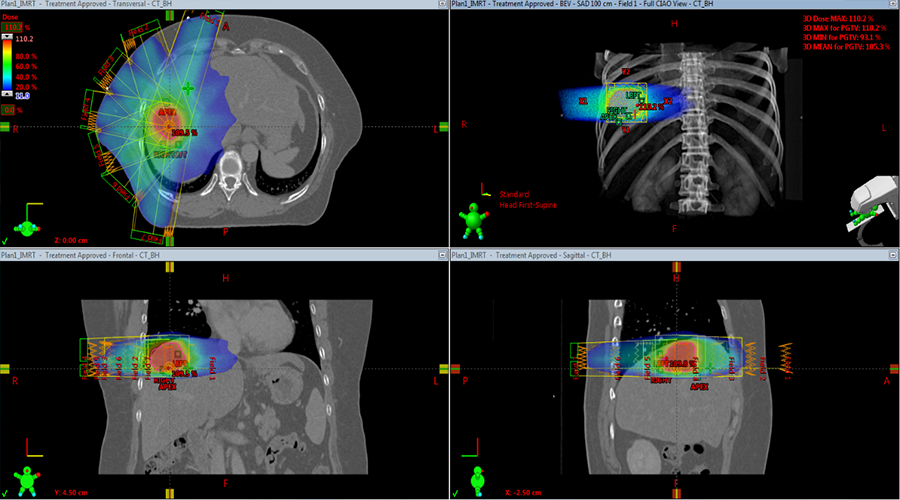

4. 物理师计划设计时标明3个电磁转发器的中心,Eclipse自动得到它们相对于等中心的坐标;并布野优化完成了一个5/7野的IMRT计划。由于PTV比常规治疗小,更容易避让危及器官和保护正常肝脏组织。

转移病例的7个野6xFFF的IMRT计划,可见肿瘤靠近膈顶,

运动幅度受呼吸影响较大